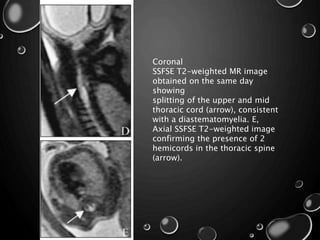

Coronal

SSFSE T2-weighted MR image

obtained on the same day

showing

splitting of the upper and mid

thoracic cord (arrow), consistent

with a diastematomyelia. E,

Axial SSFSE T2-weighted image

confirming the presence of 2

hemicords in the thoracic spine

(arrow).

Coronal SSFSE T2-weighted MRimage obtained on the same day showing splitting of the upper and mid thoracic cord (arrow), consistent with a diastematomyelia. E, Axial SSFSE T2-weighted image confirming the presence of 2 hemicords in the thoracic spine (arrow).